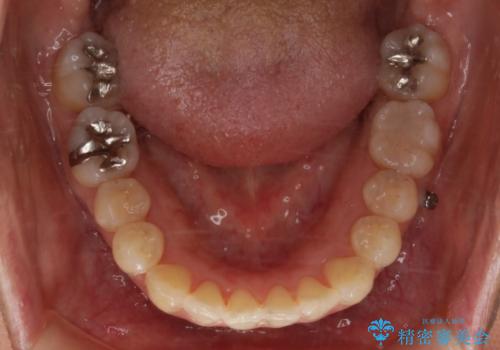

- 矯正治療が終了して歯並びが綺麗になると、元々入っていた銀歯が気になってきたとのことで適合の良いセラミックへのやり替えを行いました。

適合不良の補綴物は二次的な虫歯発生のリスクが高まります。

自費診療で用いられる材料は保険適応の材料に比べて、より精密で適合の良い被せ物作ることができるため、長期的な虫歯のリスクを大幅に減らすことが可能です。